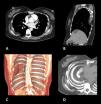

TC axial (A) y sagital (B) con contraste, con reconstrucciones (C,D), en que se observa una herniación en forma de lente convexa y una incarceración de tejido blando de la pared posterior derecha del tórax (capa de grasa subcutánea y músculo romboides mayor) en la cavidad pleural a través del espacio ensanchado existente entre la sexta y la octava costillas.

Una mujer de 45años fue ingresada con una clínica de 10días de dolor torácico en la parte posterior del lado derecho, sin otros síntomas asociados. Diez años antes se le había practicado una resección de la séptima costilla por un hemangioma costal. Se realizó una TCMD que reveló la presencia de una herniación en forma de lente convexa y una incarceración de tejido blando de la pared torácica posterior derecha (capa de grasa subcutánea y músculo romboides mayor) en la cavidad pleural a través de un espacio intercostal ampliado entre la sexta y la octava costillas (fig. 1). El cirujano torácico responsable del tratamiento optó por una toracotomía exploratoria a través de este interespacio, y en la intervención no se observó ninguna masa en la pared torácica. La incisión de toracotomía se cerró cuidadosamente con puntos fuertes para evitar una recidiva herniaria. La recuperación postoperatoria se desarrolló sin incidentes y la paciente fue dada de alta en estado asintomático.